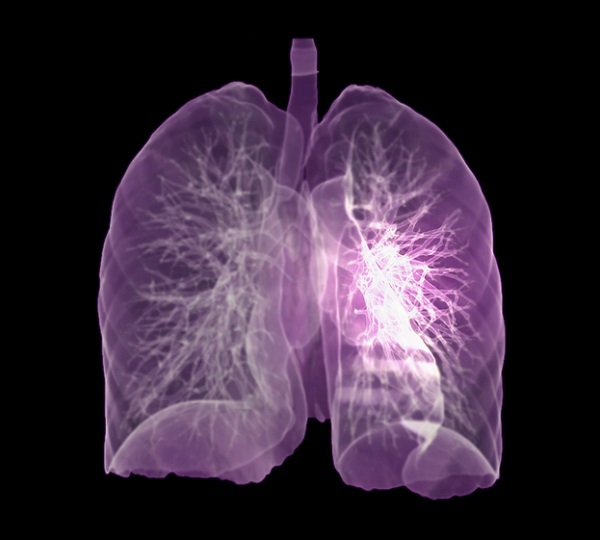

폐암은 폐에 비정상적인 암세포가 증식하여 덩어리를 형성하고 인체에 해를 미치는 것을 말합니다. 즉 폐에 생긴 악성종양을 말하며 폐 자체에 암이 발생하거나 다른 장기에서 생긴 암이 폐로 전이되어 발생합니다.

그렇다면 폐암 원인은 무엇일까요? 폐암의 가장 큰 발병 요인은 흡연입니다. 흡연자는 비 흡연자에 비해 폐암 발병확률이 15배~80배가량 높습니다.

또 다른 원인으로는 석면, 크롬 등의 물질에 노출되어 발병하거나, 대기오염과 같은 환경요인, 유전적 요인, 호흡기 질환의 과거력 등이 폐암 발병의 요인이 됩니다.